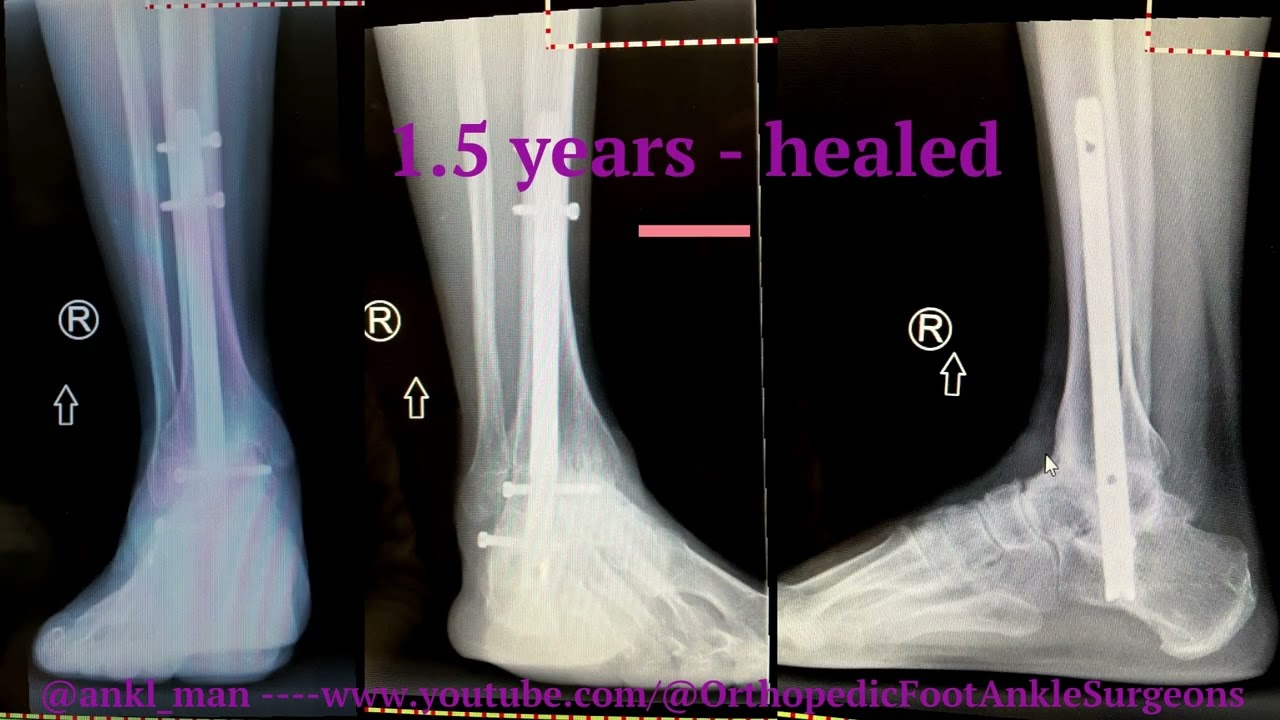

Talus Body fracture leading to Ankle and Subtalar arthritis - Tibiotalocalcaneal (TTC) Fusion Nail